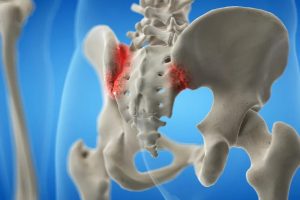

Viêm khớp cùng chậu (Sacroiliitis) là tình trạng viêm xảy ra tại một hoặc cả hai khớp cùng chậu – vị trí nối giữa xương cùng (ở cuối cột sống) và xương chậu. Đây là khu vực chịu tải trọng lớn khi đứng, đi lại hoặc nâng vật nặng, vì vậy rất dễ bị tổn thương nếu có rối loạn cơ học hoặc viêm nhiễm.

Bệnh lý: Viêm khớp cùng chậu

(Nguồn: Công ty TNHH Dược liệu Nhất Tâm)